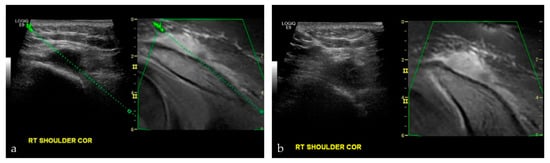

3.2.4. Targeted Percutaneous Lesion Biopsy and/or Aspiration

- Burke, C.J.; Bencardino, J.; Adler, R. The potential use of ultrasound magnetic resonance imaging fusion applicationsin musculoskeletal intervention. J. Ultrasound Med. 2017, 36, 217–224. [Google Scholar] [CrossRef] [PubMed]